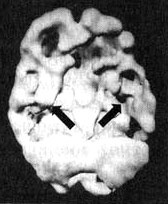

Заболевание Альцгеймера, разрушительная прогрессирующая форма старческого слабоумия, является одной из главных проблем с памятью у пожилых людей. К сожалению, у многих это заболевание крадет годы заслуженного отдыха, а их близких доводит до физического, эмоционального и финансового истощения. Действенным диагностическим методом в таких случаях оказывается SPECT. Прежде чем медикам стали доступны методы функциональной диагностики, единственным достоверным способом поставить этот диагноз было вскрытие. Сканирование SPECT показывает типичное для болезни Альцгеймера снижение перфузии в обеих височных долях и снижение активности в теменных долях. Иногда такая картина возникает за три-шесть лет до появления симптомов. Некоторые новые препараты для лечения этого заболевания, похоже, могут приостанавливать его развитие. В ходе сканирования мы наблюдали, что благодаря их действию улучшается перфузия в тех частях мозга, которые отвечают за память и мышление, в том числе и в височных долях. На иллюстрациях представлен мозг больного синдромом Альцгеймера, который стал забывчивым, часто не мог найти дорогу, когда выходил из дома, стал забывать элементарные вещи, например разучился самостоятельно одеваться и стал проявлять все больше агрессии по отношению к собственной жене. Мозг Хэрриет. Последствия энцефалита ![]() Трехмерное изображение нижней поверхности. Обратите внимание на выражений сниженную активность в обеих височных долях (см. стрелки). Болезнь Альцгеймера ![]() Трехмерное изображение поверхности, вид сверху. Обратите внимание на выраженно сниженную активность в теменных долях (см. стрелки). ![]() Трехмерное изображение нижней поверхности. Обратите внимание на выраженно сниженную активность в височных долях (см. стрелки). Говорят, что «спазмами височных долей» страдал Федор Иванович Достоевский. Он считал свою болезнь «святым переживанием». Один из его биографов, Рене Фюлеп-Миллер, цитирует высказывание Достоевского, что эпилепсия «вызывает во мне чувства, о которых я доселе не подозревал, сообщая мне ощущения блаженства, изобилия и вечности». В своем романе «Идиот» Достоевский пишет: «Он задумался между прочим о том, что в эпилептическом состоянии его была одна степень почти пред самым припадком (если только припадок приходил наяву), когда вдруг, среди грусти, душевного мрака, давления, мгновениями как бы воспламенялся его мозг, и с необыкновенным порывом напрягались разом все жизненные силы его. Ощущение жизни, самосознания почти удесятерялось в эти мгновения, продолжавшиеся как молния. Ум, сердце озарялись необыкновенным светом; все волнения, все сомнения его, все беспокойства как бы умиротворялись разом, разрешались в какое-то высшее спокойствие, полное ясной, гармоничной радости и надежды, полное разума и окончательной причины. Но эти моменты, эти проблески были еще только предчувствием той окончательной секунды (никогда не более секунды), с которой начинался настоящий припадок. Эта секунда была, конечно, невыносима. Раздумывая об этом мгновении впоследствии, уже в здоровом состоянии, он часто говорил сам себе, что ведь все эти молнии и проблески высшего самоощущения и самосознания, а стало быть и „высшего бытия“, не что иное как болезнь, как нарушение нормального состояния, а если так, то это вовсе не высшее бытие, а, напротив, должно быть причислено к самому низшему. И однако же, он все-таки дошел наконец до чрезвычайно парадоксального вывода: „что же в том, что это болезнь?“, решил он наконец, „какое до того дело, что это напряжение ненормальное, если самый результат, если минута ощущения, припоминаемая и рассматриваемая уже в здоровом состоянии, оказывается в высшей степени гармонией, красотой, дает неслыханное и негаданное дотоле чувство полноты, меры, примирения и встревоженного молитвенного слития с самым высшим синтезом жизни?“». Брайс Льюис Кэрролл, по некоторым свидетельствам, тоже страдал «явлениями от височных долей», которые хорошо отражены в зрительных образах Алисы в его книге «Алиса в стране чудес». Семилетний Брайс, которому мать стала читать «Алису», очень разволновался. Он сказал, что чувствует себя как Алиса. «Со мной происходят странные вещи, — рассказал он матери. — Я вижу всякие вещи». Среди бела дня он наблюдал, как предметы меняют свою форму, часто уменьшаясь в размерах. Ночью он видел зеленоватых призраков. У Брайса обнаружилось много симптомов тревожности. Его мать, перепугавшись, что Брайс «сходит с ума» (а его двоюродному брату поставили диагноз «шизофреноподобное состояние»), мать привела его ко мне на прием. Услышав о его симптомах, я заподозрил, что одна или обе височные доли у него гиперактивны. Сканирование SPECT выявило нарушения в правой височной доле и повышенную активность базальных ганглиев. Я назначил Dapakote (противосудорожный препарат, эффективный при лечении поражений височных долей), а также сеансы психотерапии для снижения тревожности. В течение двух недель странные состояния Брайса прекратились, а в течение полугода снизилась и тревожность. Мозг Брайса. Эпилепсия височных долей ![]() Трехмерное изображение нижней поверхности. Обратите внимание на область повышенной активности в глубоких отделах правой височной доли (стрелка снизу вверх) и базальных ганглиях (стрелки вниз). Эллен и Джек У Эллен и Джека похожие истории болезни. Оба были слегка замкнутыми. У обоих случались приступы головокружения и беспричинной паники. У обоих религиозный опыт занимал довольно значительное место в жизни. У Эллен (32 года) глубокие религиозные переживания практически парализовали ее жизнь. Она не могла работать и находилась в социальной изоляции. Джека очень заинтересовали ее «периоды глубокого духовного просветления», но он никак не мог понять, что это означает. Ко мне на прием Эллен привели ее родители, которых беспокоила ее социальная изолированность. Джек хотел обследоваться по поводу приступов паники. В обоих случаях сканирование выявило выраженную гиперактивность глубинных областей в височных долях. Значительная часть их симптомов ушла после того, как они начали принимать Depakote. При этом, продолжая прием этого препарата, оба остаются глубоко религиозными людьми. Правда, они больше не остаются погруженными в свои мысли значительную часть времени, как это было раньше. Джим Как в случае Эллен и Джека, Джима беспокоили приступы головокружения и панического страха. У него тоже бывали периоды «религиозных мыслей», во время которых он ощущал «присутствие дьявола», становился неуверенным и напуганным. Его страх перед дьяволом преследовал его, делал замкнутым. В семье считали, что он страдает паранойей. В результатах сканирования мозга Джима выявилось интересное отличие от результатов Эллен и Джека. У Джима нарушения обнаружились в левой, а не в правой височной доле. На основании своего опыта я полагаю, что нарушения именно в левой височной доле проявляются особенно негативными или мрачными мыслями. После того как Джим стал принимать Depakote, «присутствие дьявола» завершилось. |